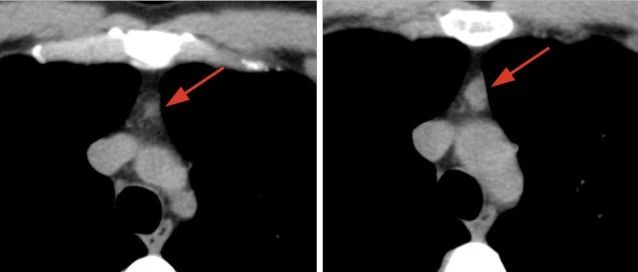

胸腺瘤的影像学现状

胸腺上皮性肿瘤是指来源于胸腺上皮组织的恶性肿瘤,占全部恶性肿瘤0.2%~1.5%,是前纵隔最常见原发性肿瘤,包括胸腺瘤,胸腺癌和胸腺神经内分泌肿瘤,异位胸腺瘤可发生在颈部、中纵隔、后纵隔、肺和胸膜,少数文献报道了巨大胸腔内肿瘤,但仅占全部胸腺瘤的4%。